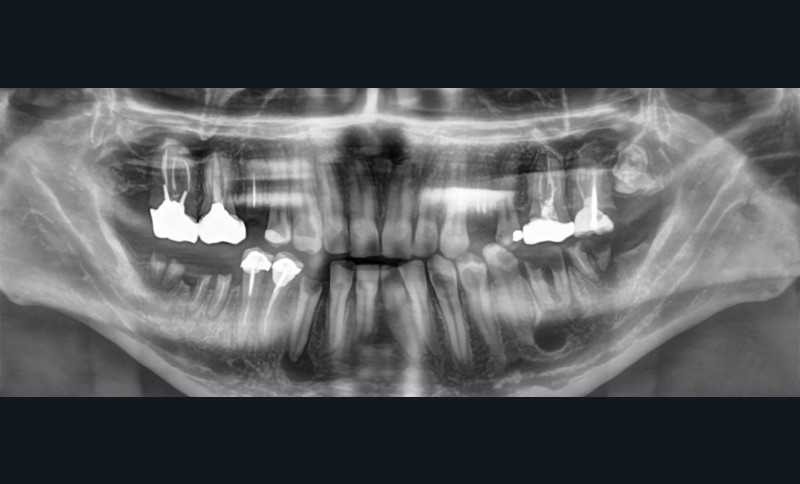

On distingue classiquement le granulome (- 1 cm) du kyste (+ 1 cm). Ce dernier possède des parois propres et des contours réguliers bien délimités. Le développement kystique s’accompagne volontiers d’un refoulement des structures avoisinantes, les corticales osseuses apparaissent soufflées, dans certains cas, amincies, pouvant venir empiéter sur des éléments anatomiques de la sphère maxillo-mandibulaire (sinus, canal mandibulaire, fosses nasales, foramen mentonnier…) (fig. 3).

L’exérèse d’un kyste nécessite-t-elle toujours l’avulsion de la dent causale ?

Dans la majorité des cas, l’énucléation kystique s’accompagne de l’extraction de la dent causale. Toutefois, en présence de dent conservable sur le plan prothétique, une chirurgie endodontique (obturation a retro…